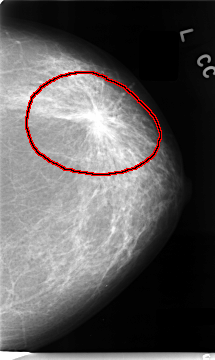

C_0089_1.LEFT_MLO

LEFT_MLO LINES 4728 PIXELS_PER_LINE 2776 BITS_PER_PIXEL 12 RESOLUTION 50 OVERLAY

FILE: C_0089_1.LEFT_MLO.OVERLAY

TOTAL_ABNORMALITIES 1

ABNORMALITY 1

LESION_TYPE MASS SHAPE IRREGULAR MARGINS SPICULATED

ASSESSMENT 5

SUBTLETY 5

PATHOLOGY MALIGNANT

TOTAL_OUTLINES 1

BOUNDARY